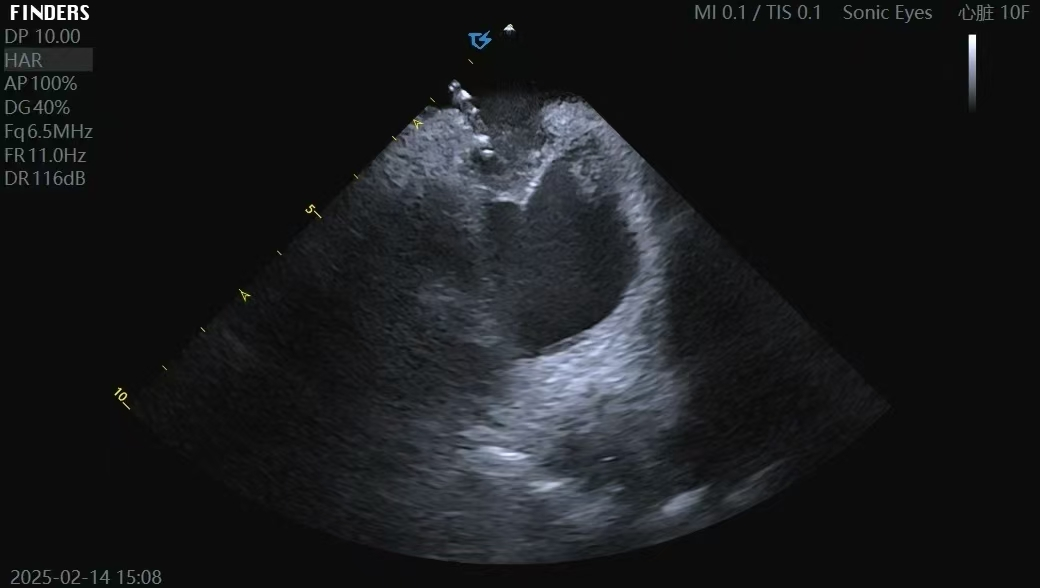

ICE指导零造影剂房间隔穿刺术

心腔内超声导管(ICE)技术是经血管置入心脏内部,实时提供高分辨率超声影像的导管技术。该技术具有以下优势:(1)ICE导管可360°旋转,灵活获取心脏长轴、短轴、四腔心等多切面影像,多角度成像,突破传统超声局限,精准引导复杂解剖结构;(2)ICE可替代传统X线透视引导,减少患者和手术医生的X射线暴露、很好地保护了孕妇、儿童、肝肾功能不全和造影剂过敏患者;(3)无需全身麻醉,降低围术期风险,适用于高危患者(如严重肺病、血流动力学不稳定),缩短术前准备及术后恢复时间;(4)具有实时成像功能,可全程监测心包积液,早期预警心脏穿孔,提高手术的安全性。